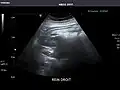

Right kidney -

Kidneys: Right and left kidneys measure 11.5 cm and 12 cm in length respectively. No hydronephrosis. Small left lower pole kidney cyst.